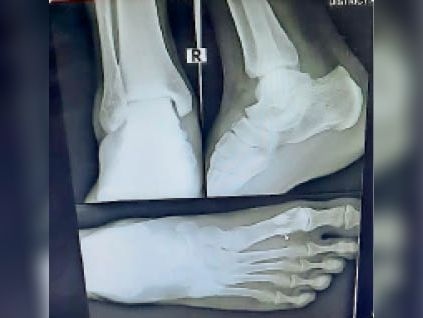

बुजुर्ग महिला का पैर चार जगह से टूटा, दर्दनाक हादसे से मचा हड़कंप

दिल्ली| ग्रेटर नोएडा वेस्ट की सुपरटेक ईकोविलेज एक सोसायटी में बिजली जाने से लिफ्ट 13वीं से आठवीं मंजिल पर जाकर गिर गई। लिफ्ट में सवार 65 वर्ष की बुजुर्ग महिला अपने नाती और नातिन के साथ थीं। लिफ्ट गिरने से बुजुर्ग महिला के पैर में चार फ्रैक्चर हुए हैं। आरोप है कि बुजुर्ग को मौके पर व्हीलचेयर तक नहीं मिलीं। वह किसी तरह अपने घर तक पहुंची। उन्होंने परिवार के लोगों को घटना के बारे में बताया। परिवार के लोग उपचार के लिए उन्हें अस्पताल ले गए। जहां एक्सरे कराने पर चार फ्रैक्चर की पुष्टि हुई है। निवासियों ने बताया कि रीना प्रसाद (65) एफ 7 टावर में अपने परिवार के साथ रहतीं हैं। बुजुर्ग महिला रीना के पति उमेश्वर प्रसाद ने बताया उनके 11 और सात वर्षीय नातिन और नाती जी 5 टावर में ट्यूशन जाते हैं। सोमवार को शाम करीब पांच बजे रानी प्रसाद नाती नातिन को लेने गईं थी। लिफ्ट से वह दोनों को लेकर लौट रहीं थीं। 13 वीं मंजिल पर जैसे ही लिफ्ट पहुंची इसी दौरान बिजली चली गई। बिजली जाने के बाद लिफ्ट गिरकर सीधे आठवीं मंजिल पर पहुंची। बच्चे और रानी तीनों लिफ्ट के फ्लोर पर गिर गए। किसी तरह तीनों संभले। लिफ्ट ग्राउंड फ्लोर पर पहुंची तो रानी उससे बाहर नहीं निकल पा रहीं थीं। दोनों बच्चे बुरी तरह घबराए हुए थे। गार्ड से व्हीलचेयर मांगी तो वो भी टावर में नहीं थी। अस्पताल पहुंचने पर हुए एक्सरे में चार जगह पैर में फ्रैक्चर निकला। पैर पर प्लास्टर कराकर वह अपने घर लौटीं। उमेश्वर प्रसाद ने बताया कि अभी थाने में कोई शिकायत नहीं दी गई है। लिफ्ट एक्ट लागू होने के बाद भी ईकोविलेज 1 सोसायटी में लिफ्ट को लेकर समस्याएं लगातार बनी हुईं हैं। लोगों की ओर से कई बार थाने में शिकायत दी गईं। एक्ट के मुताबिक लिफ्ट और एस्केलेटर का पंजीकरण कराना अनिवार्य है। लिफ्ट में था यूपीएस, तकनीकी खामी से गिरी इकोविलेज एक सोसायटी के 52 टॉवर में करीब 97 लिफ्ट हैं। सभी में यूपीएस लगे हैं। बिजली जाने के बाद लिफ्ट गिरने की घटना तकनीकी खराबी से हुई। बिजली जाने पर यूपीएस की मदद से लिफ्ट नजदीकी फ्लोर पर जाकर रुकती है और वहां पर खुल जाती है।